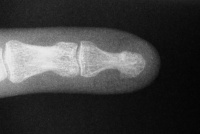

| Case 2. 3 month old grossly unstable nonunion. |

| The new nail plate

is visible growing deep to the original nail plate. |